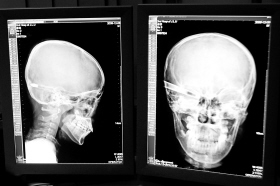

在接受x光檢查的小沖

“還是先做個(gè)X光透視,看一下箭桿到底有多深。”眼科醫(yī)生緊急趕到CT室查看,和放射科的幾位醫(yī)生共同研究后,決定先讓小沖做X光透視。

“如果再用點(diǎn)力,就從后腦穿出來了!”由于小沖無法移動(dòng),醫(yī)生拿來移動(dòng)插座,將透視的光板放在小沖的移動(dòng)病床上,透視后讓在場(chǎng)的醫(yī)生都吃了一驚:箭桿直接穿過了大腦和小腦,箭尖兒直抵后顱骨,足足有10余厘米。